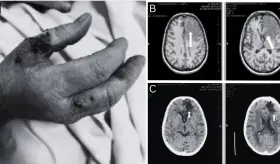

El paciente no tenía factores de riesgo ni inmunosupresión, lo que hizo aún más inusual el desarrollo de la infección.

La reactivación ocurrió en el contexto de un aumento en la inmunosupresión, específicamente con el incremento del micofenolato mofetilo (MMF).